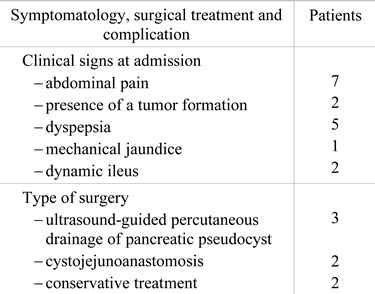

The position of the pseudocyst in the tail of the pancreas in direct contact with the space of the left renal bed allowed us to perform an ultrasound-guided incision in the left lumbar area by draining the pseudocyst’s content through drainage tubes with a thick diameter, under intravenously induced anesthesia potentiated locally with Xylin 1% (Figure 2).

Figure 2.

Drainage tubes inserted into the left renal bed after the drainage of the pseudocyst by ultrasound guided puncture in the left lumbar area, with the evacuation of cloudy fluid.

The efficiency of the external drainage of the pancreatic pseudocyst by inserting drainage tubes in the left lumbar area was favorable, with the persistence of evacuating the contents of the pseudocyst for a longer time of about 3 months, but with the decrease of the flow until its disappearance.